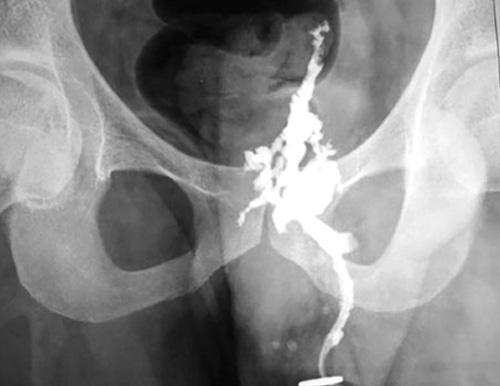

HSG

Hysterosalpingography, also known as uterosalpingography, is a radiologic procedure to investigate the shape of the uterine cavity and the shape and patency of the Fallopian tubes. It is a special x-ray using dye to look at the womb and Fallopian tubes.